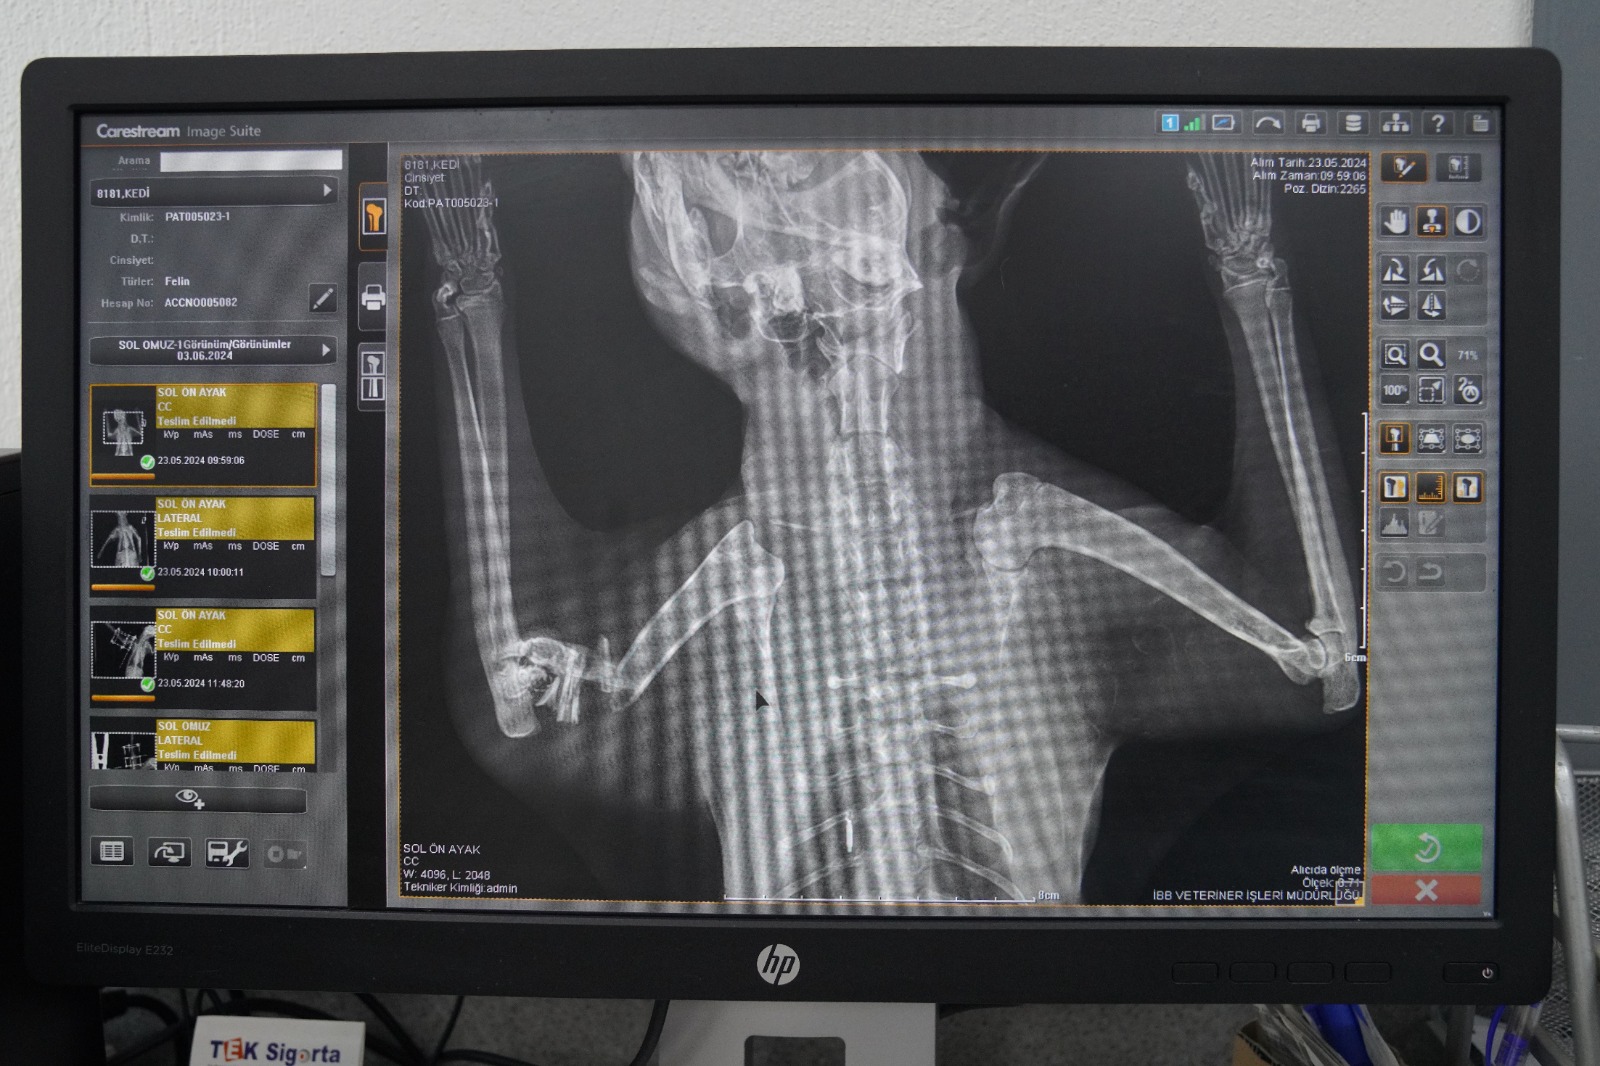

Ameliyat hakkında bilgi veren Veteriner Hekim Mehmet Uysal, ortopedi biriminde kedinin bacağının durumunu tespit ettiklerini belirterek, “Bacağının ciddi şekilde parçalandığını gördük. Burada sağlığına kavuşması için hemen gerekli cerrahi tedaviyi uyguladık. Bacağında parçalanan kemikleri özel bir aparatla sabitledik. Güvenli bir yöntem olduğu için bunu tercih ettik. Kedimiz 25 gündür bu şekilde tedavi altında. Bir süre sonra bu taktığımız aparatın kırıklar üzerindeki etkisine bakacağız. Bacak iyileşmiş olursa çıkaracağız. Şu anda sağlığı ile alakalı bir problemi yok. Keyfi yerinde. Bacağını nasıl kullanacağını öğreniyor diyebilirim” diye konuştu.